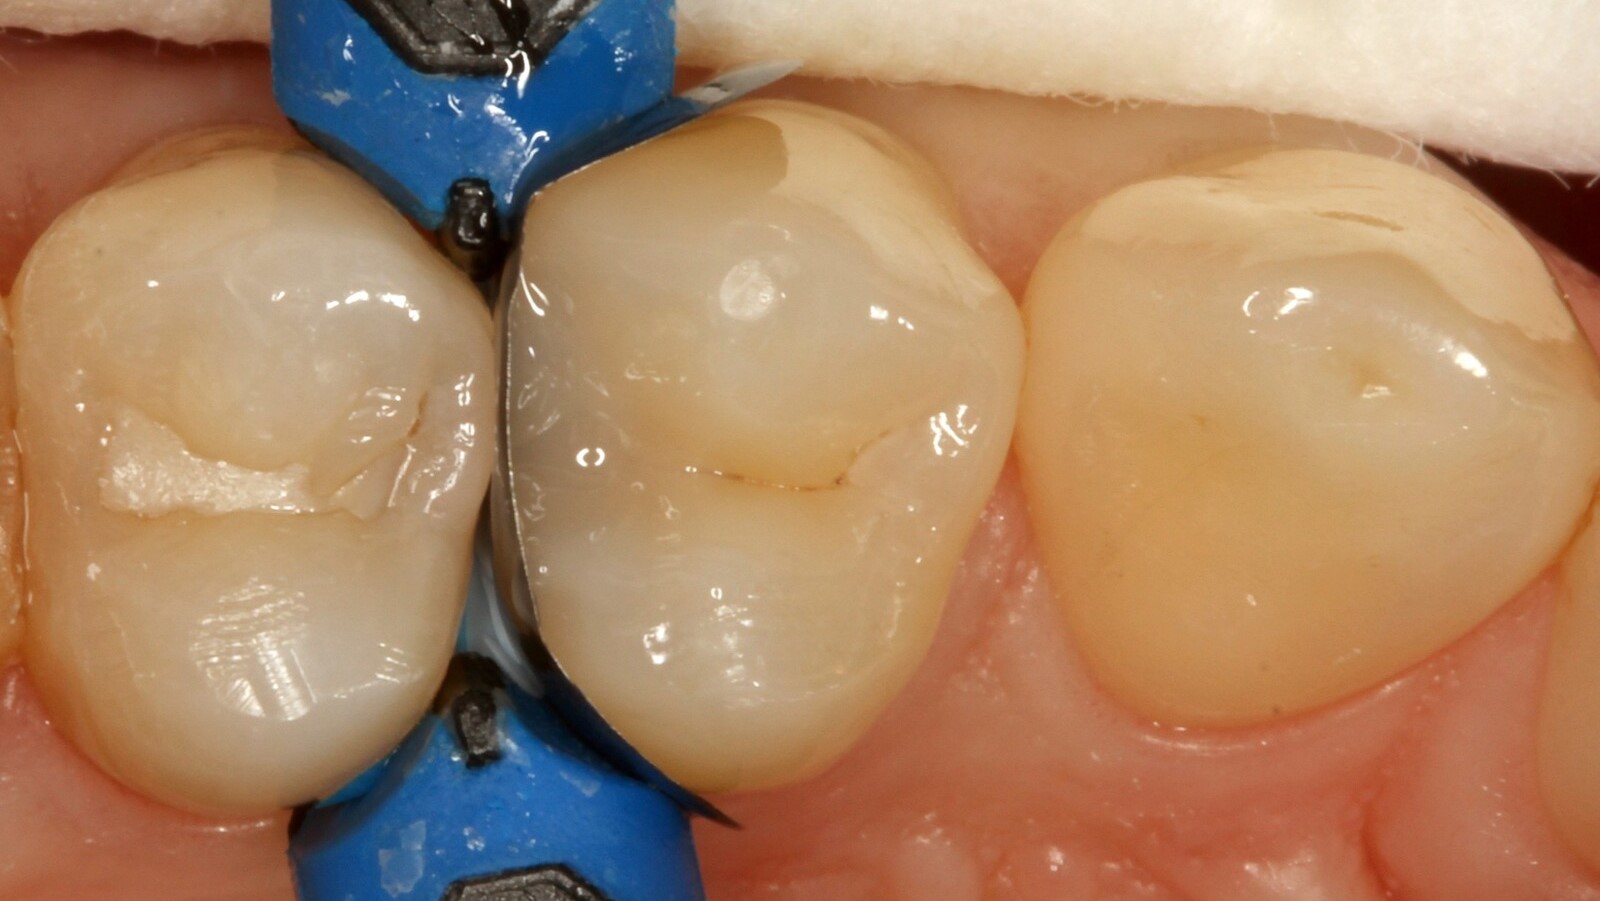

Professor Ernst first identified the hidden caries and opened the carious lesion to show the patient the problem (Fig. 1-2). He then excavated the caries, prepared the cavity and placed a sectional matrix (Fig. 3) before sealing the cavity with adhesive (Fig. 4). In a single step, he filled the cavity with Venus Bulk Flow ONE (Fig. 5). Once the restoration was completed, Prof. Ernst polished it (Fig. 6) and took a control radiograph, which also shows the excellent radiopacity of Venus Bulk Flow ONE (Fig. 7).

Venus Bulk Flow ONE is a new dental composite that provides a single shade bulk filling solution without the need for additional layering. Its flowable consistency makes it easy to handle and its bulk-fill properties allow it to be used in increments of up to 4mm, making it the ideal composite for dentists looking for a fast and efficient restoration process. It also matches any tooth shade from A1 to D4, ensuring a seamless and natural appearance.